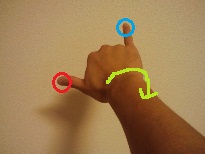

まず、右手を顔の高さで、前方にしっかりと伸ばします。

次に、写真のように、親指と小指のみを軽く伸ばします。

左目を閉じて、右目で、親指の爪(赤丸)をじっと見つめます。

小指が上の方を向いている時には、親指の爪を見ていても、小指の先(青丸)も視野の中で認識が出来ると思います。

そこから、親指の爪を見たままの状態で、腕を時計回りにゆっくりと回していき、小指が親指と水平の部位に来るようにします。

こんな感じ。すると、親指の爪を見ていると、小指が見えなくなっていると思います。この見えない範囲がマリオット盲点です。